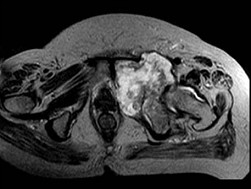

[单选题]患者,男,38岁,左髋部疼痛,并逐渐加重,体检:左髋部明显肿胀压痛,无明显发热,结合所提供的图片,最可能的诊断是()A .骨巨细胞瘤B .纤维肉瘤C .骨肉瘤D .软骨肉瘤E .软骨黏液纤维瘤

[单选题]患者,男,38岁,左髋部疼痛,并逐渐加重,体检:左髋部明显肿胀压痛,无明显发热,结合所提供的图片,最可能的诊断是()A . 骨巨细胞瘤B . 纤维肉瘤C . 骨肉瘤D . 软骨肉瘤E . 软骨黏液纤维瘤